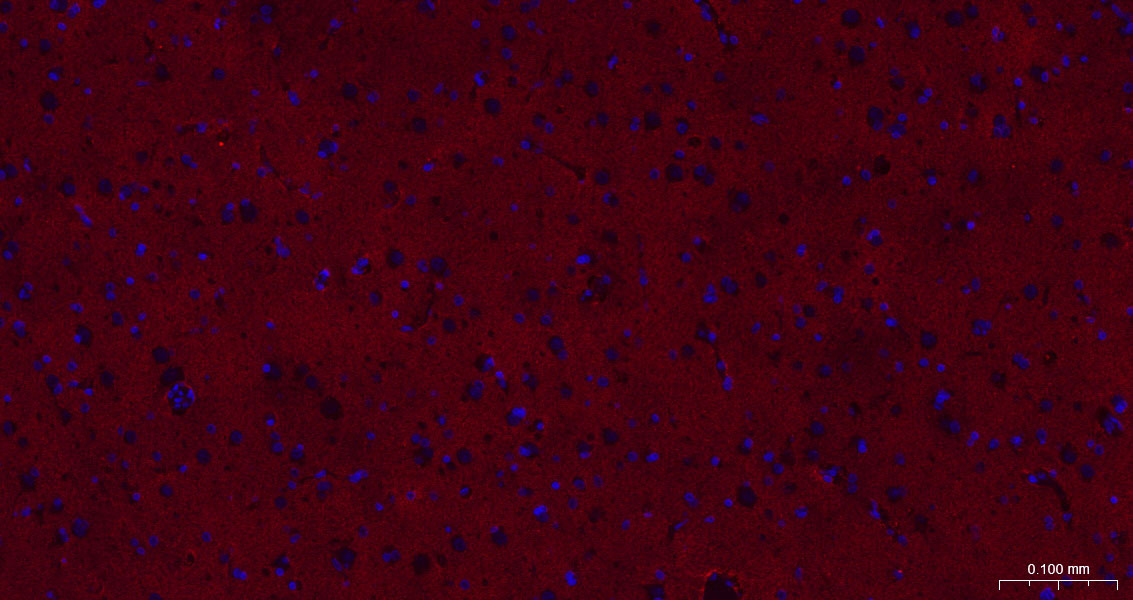

Paraformaldehyde-fixed, paraffin embedded Mouse Cerebellum; Antigen retrieval by boiling in sodium citrate buffer (pH6.0) for 15 min; The section was incubated with EAAT1 Monoclonal Antibody, Unconjugated (bsm-60880R) at 1:200 overnight at 4°C. Followed by conjugated Goat Anti-Rabbit IgG antibody (Red, bs-0295G-BF594), DAPI (blue, C02-04002) was used to stain the cell nuclei.